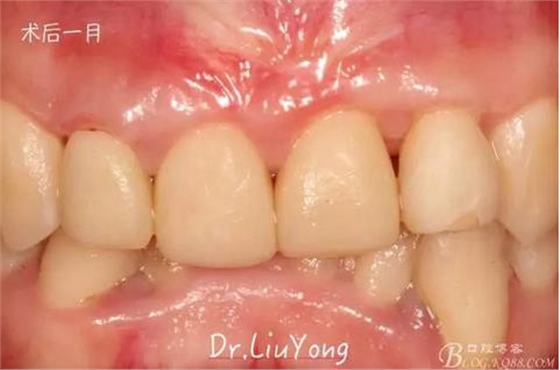

臨時修復(fù)體戴入后1月,復(fù)查,唇側(cè)觀如上圖

膜齦手術(shù)后2月復(fù)查,可以明顯觀察到,B12之間的牙齦乳頭明顯高度增加,黑三角得到很大改善,如下圖: